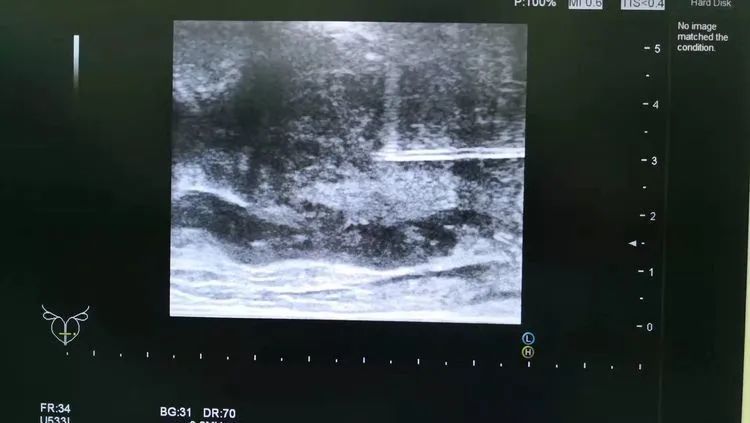

前列腺穿刺活檢是通過非常細的特制穿刺針(直徑1mm左右)獲取前列腺組織進行病理學檢查,是目前診斷前列腺癌最為有效的方法。

為更好的服務大衆,开云体育引進了國際上先進的日立阿洛卡彩超機及經直腸雙平面超聲探頭,現已成熟開展彩超引導下經會陰前列腺穿刺活檢,與北京、上海、合肥等三甲大醫院成功接軌。

患者李先生,56歲,8月前發現PSA值輕度升高,先後在外院就診數次,均未明确診斷,建議随訪觀察。今年2月來到开云体育總院泌尿外科行彩超引導下經會陰前列腺穿刺活檢,穿刺順利。術後病理提示為前列腺腺癌,Gleason評分3+4。後行前列腺癌根治性切除術,術後恢複佳,現已出院。